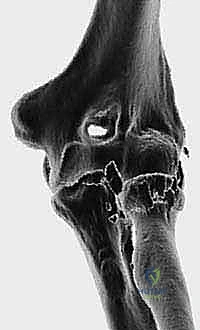

* الكسور المفتتة بشدة (Comminuted Fractures): عندما ينكسر رأس الكعبرة إلى أكثر من ثلاث قطع صغيرة جداً لا يمكن تجميعها وتثبيتها بالمسامير.

* الثالوث الرهيب لمفصل الكوع (Terrible Triad of the Elbow): وهي إصابة كارثية تتضمن: خلع في مفصل الكوع، كسر في رأس الكعبرة، وكسر في الناتئ الإكليلي (Coronoid). في هذه الحالة، استبدال رأس الكعبرة ضروري لإنقاذ الكوع من الخلع المتكرر.

* إصابات إيسيكس-لوبريستي (Essex-Lopresti Lesion): كسر رأس الكعبرة المصحوب بتمزق الغشاء بين العظام وصولاً إلى مفصل الرسغ.

* الفشل الجراحي السابق: فشل عمليات التثبيت الداخلي (الشرائح والمسامير) السابقة، مما أدى إلى نخر انعدام الدم (Avascular Necrosis) أو عدم التئام الكسر.